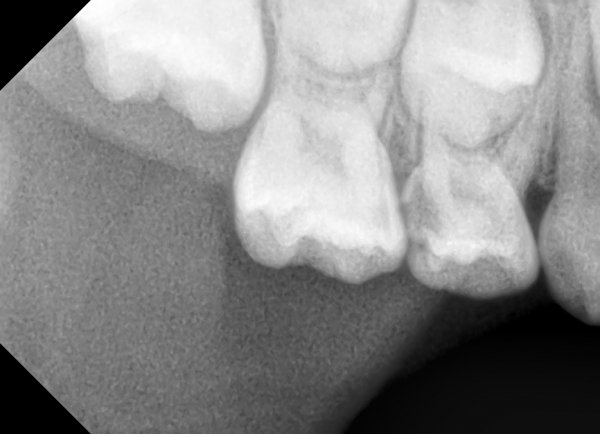

Доброе утро! Мне делали снимок в 14 лет, сказали у меня молочные зубы еще 2. Сказали сами выпадут. Сейчас мне уже почти 19. Один только шатается, болит жуть как. И над ним шишечка на десне, белая немного. Мне его нужно выдирать или сам выпадет? И еще я проживаю м.Петровско-Разумовская, Дмитровское шоссе 43-1. Мне если что в вашу поликлинику идти? Просто с детской, я так ни разу и не ходила к стоматологу.

Шишечка - это воспаление, зуб необходимо удалить.